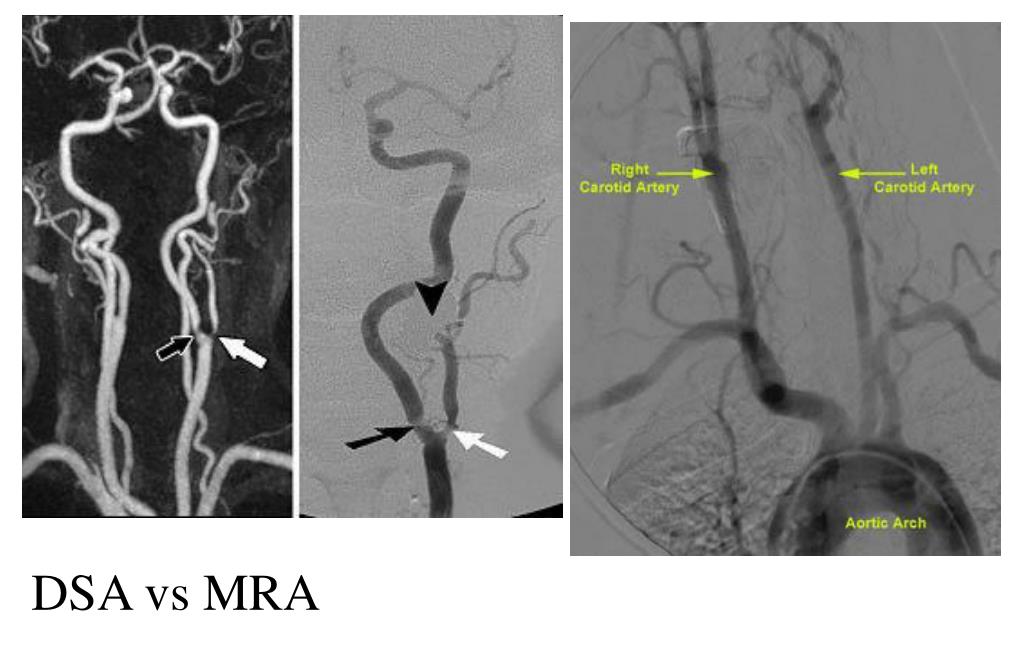

35. DSA vs MRA

36. 磁共振血管造影